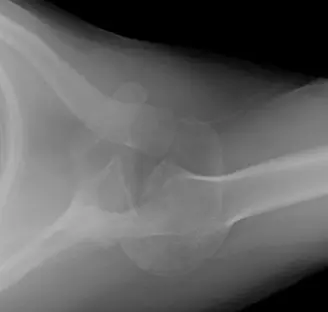

1. الأشعة السينية (X-rays)

على الرغم من أن الأشعة السينية الأولية قد تكون فاتتها الخلع، إلا أن الصور الشعاعية المناسبة يمكن أن تكشفه بوضوح. يجب الحصول على عدة مناظر:

- المنظر الأمامي الخلفي (AP Glenoid View): يُظهر رأس عظم العضد منزاحاً إلى الأمام والوسط نسبةً إلى تجويف الحُق، وغالباً ما يكون أسفل الناتئ الغرابي.

- المنظر المحوري (Axillary View): هذا المنظر حاسم لتأكيد اتجاه الخلع (أمامياً، خلفياً، أو سفلياً) ويُظهر رأس عظم العضد بوضوح أمام تجويف الحُق. كما يسمح بتقييم مبدئي لفقدان العظم في الحُق.

- منظر Y-Scapular View: يُظهر رأس عظم العضد أمام نقطة تقاطع شكل الحرف Y، مؤكداً الخلع الأمامي.

(الشكل 1: صورة أشعة سينية أولية تظهر خلع الكتف الأمامي السفلي.)